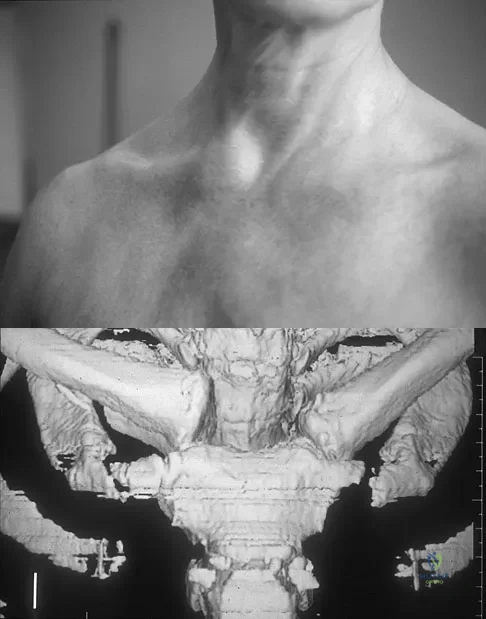

Question 38High Yield

Figure 11a shows the clinical photograph of a 46-year old woman who reports a 3-week history of pain and a "lump" at the base of her neck. She is otherwise in good health and denies any trauma. A 3-D reconstruction CT is shown in Figure 11b. What is the most likely diagnosis?

Explanation